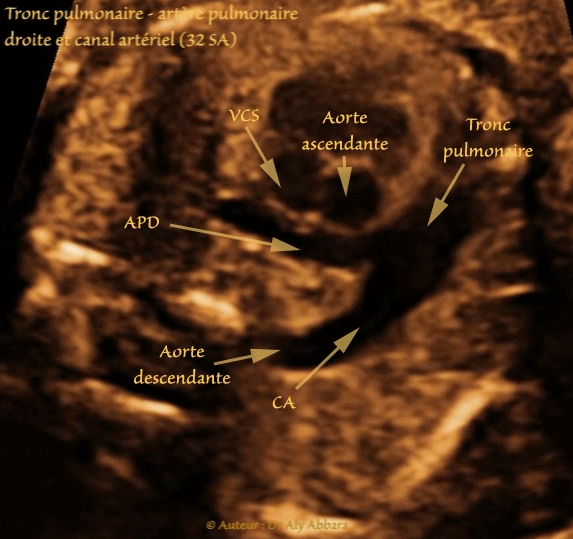

• Cœur fœtal à 32 SA : coupe du tronc pulmonaire et ses branches

• Cette image est l'illustration parfaite de la description anatomique suivante :

• Au-dessous de la crosse de l'aorte le tronc pulmonaire se divise en artères pulmonaires droite et gauche et en canal artériel.

• L'artère pulmonaire droite (APD) est plus longue et plus large que l'artère pulmonaire gauche ; elle chemine vers la droite horizontalement derrière l'aorte ascendante " Croisement de l'aorte et l'artère pulmonaire droite " et derrière de la veine cave supérieure avant d'atteindre le hile du poumon droit.

• L'artère pulmonaire gauche (APG) chemine horizontalement vers la gauche, à l'avant de l'aorte descendante.